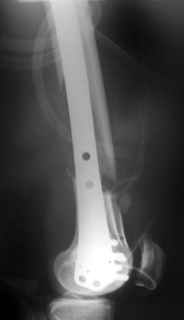

Look what we would have done.